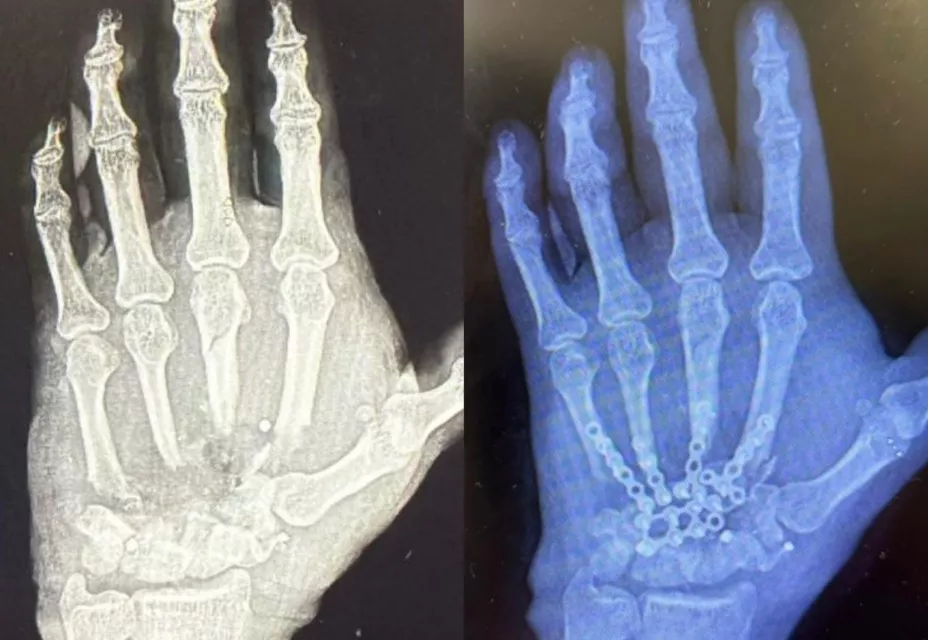

“Aparte de la reconstrucción del hueso, de reconstrucción de los tejidos blandos, se le hizo una cobertura cutánea, entonces se le tomó un injerto para cubrir la totalidad de la herida, por lo que prácticamente el paciente salió otra vez con huesos de la mano, con movilidad, con buena circulación, y con la cobertura total de la herida”, subrayó.

La jefa del Departamento de Cirugía Plástica, Estética y Reconstructiva del HR “Dra. Matilde Petra Montoya Lafragua” del ISSSTE, Annel Ivonne González López, destacó que, tras la cirugía, que duró aproximadamente siete horas, se logró recuperar un 75 por ciento de la movilidad de esta extremidad.